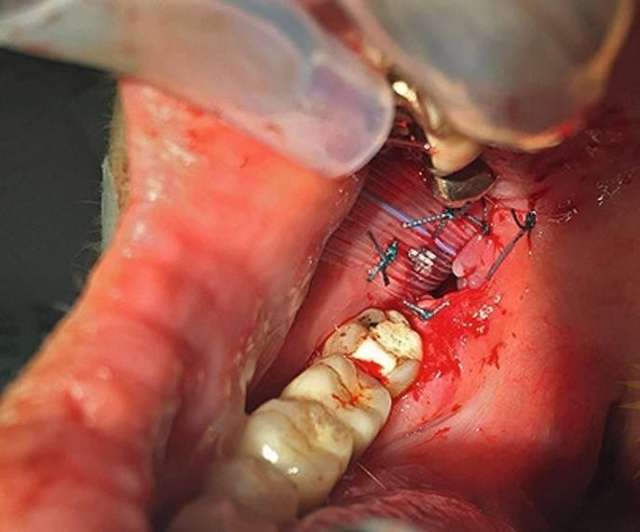

LifestyleՀամբուրգի 65-ամյա բնակչուհին դիմեց բժիշկներին՝ ասելով, որ չի կարողանում գտնել ատամները լվանալու ժամանակ կորցրած էլեկտրական խոզանակի կտորը: Բժիշկները նախ հետազոտեցին կնոջ ստամոքսն ու աղիները, բայց ոչինչ չհայտնաբերեցին և նրան ուղարկեցին տուն: Բայց մի քանի օր անց կինը կրկին դիմեց հիվանդանոց՝ գանգատվելով, որ ոչինչ չի կարողանում ուտել: Դիմածնոտային վիրաբույժը կնոջ բերանի խոռոչի փափուկ հյուսվածքներում 6 սմ երկարությամբ օտար առարկա նկատեց: Պարզվեց, որ դա հենց ատամի խոզանակի ջարդված կտորն էր: Վիրահատությունից հետո մի քանի օր անց կինը դուրս գրվեց: